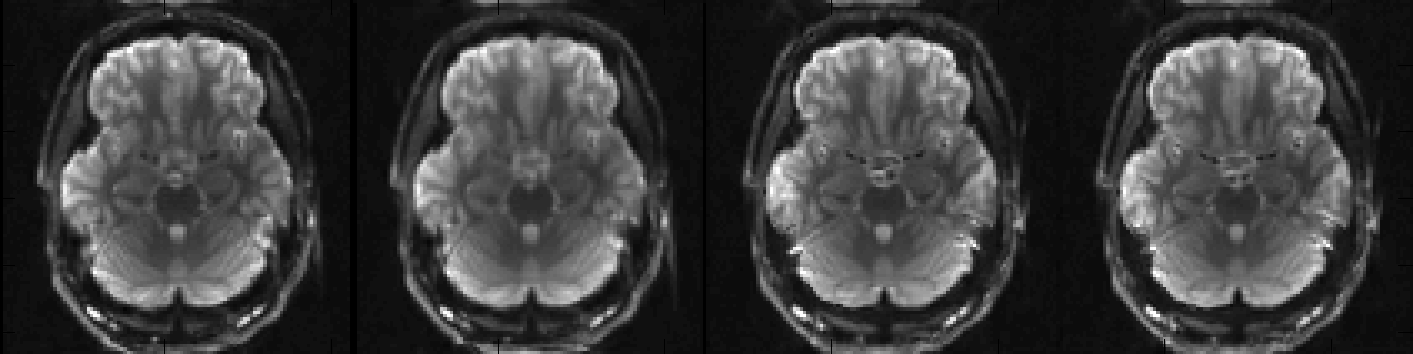

Above you can see a selected slice from the four volumes in an example file called my_b0_images.nii.gz. It is immediately obvious that the distortions in the first two images are vastly different from those in the two last images. If we take a look at the associated acqparams.txt file

we can see why. The two first images have been acquired with negative phase-encode blips in the y-direction, which means that signal from an area with "higher than expected" field (such as just above the ear-canals) will be displaced downwards. Conversely the two last images have been acquired with positive blips which means that signal from those same areas would be displaced upwards.

In addition to that we can see that the second image looks a little bit different to the first, despite having been acquired with identical parameters. This may mean that the subject moved between the acquisitions of the two images.